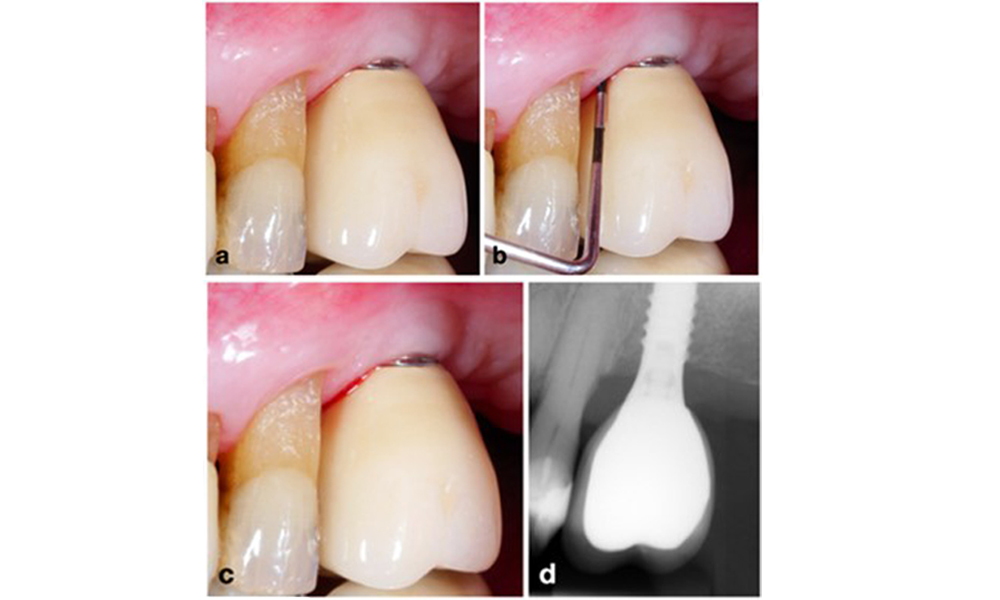

Peri-implantitis is identified by (1) signs of inflammation similar to mucositis, (2) radiographic evidence of bone loss after initial healing and (3) an increase in probing depth compared to measurements taken shortly after placing the prosthetic reconstruction (figure 2). In the absence of previous radiographs, radiographic bone level of ≥ 3 mm along with bleeding on probing and probing depths ≥ 6 mm, indicates peri‐implantitis.

Full-arch restoration with peri-implantitis of varying degrees at some implants. The implant in position 21 is severely affected with probing depths up to 9 mm (a), bleeding on probing, and suppuration from the peri-implant sulcus and a vestibular fistula (b–c); the radiograph shows approximately 50 % bone loss for the implant with peri-implantitis in position 21, while the implant in position 23 shows limited bone loss, corresponding approximately to what can be expected after initial healing for this type of implants (d).

Figure 2. Full-arch restoration with peri-implantitis of varying degrees at some implants. The implant in position 21 is severely affected with probing depths up to 9 mm (a), bleeding on probing, and suppuration from the peri-implant sulcus and a vestibular fistula (b–c); the radiograph shows approximately 50 % bone loss for the implant with peri-implantitis in position 21, while the implant in position 23 shows limited bone loss, corresponding approximately to what can be expected after initial healing for this type of implants (d).

The expected bone loss after initial healing attributed to marginal bone remodelling, varies based on factors such as the implant system or type. For instance, 1–2 mm bone loss is generally considered “normal” for bone level implants with an external connection (figure 2d, implant in position 23).